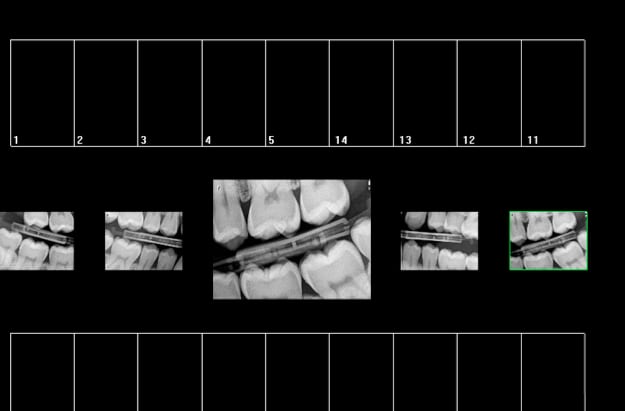

On cote quoi là ? -)

25 36 ? -)

Exemple type de radio rétro coronaire avec capteur, les 34, 44 sont difficiles à avoir.

Les rebords rétro alvéolaires aussi on a du mal a bien centrer le plan occlusal.

Capture d e cran 2016 02 18 09.18 - Eugenol

Désolé je ne vois pas la face distale de la 37.

La radio est centrée sur du vide, elle doit être centrée sur une dent.

Le patient a la bouche mal fermée, rien ne dit que je vois les antagonistes

Pourquoi avez vous fait cette radio?

"Par secteur de 1 à 3 dents contigües on entend : secteur de 1 ou 2 ou 3 dents comprenant la dent sur laquelle est centré le cliché radiographique et chacune de ses dents adjacentes. "

C'est la définition d'un secteur, il n'est écrit nulle part que toutes les dents du secteur doivent etre sur le cliché.

centrée sur du vide, elle doit être centrée sur une dent.

rétro coronaire on a du mal à savoir sur laquelle des dents antagonistes, elle est centrée.

Vous pouvez préciser ? Vous pensez que ce sont les dents du secteur 4 et non pas du secteur 3 ?

Recommandations HAS.